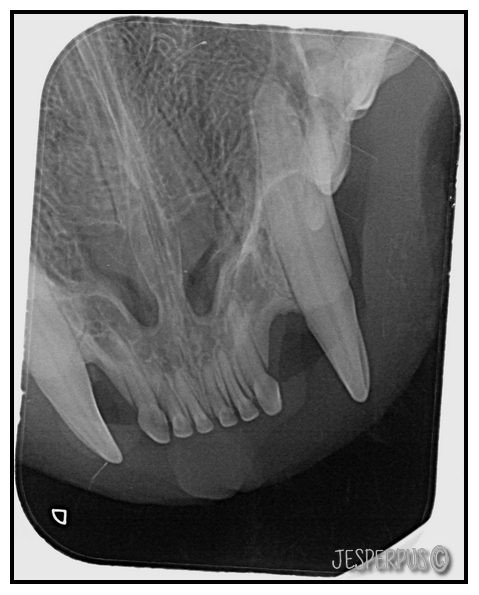

Men for å være helt sikkert, ble det tatt røntgen av alle tennene mine:

Se og røntgenbilder av katt med alvorlig TR under, tennene er nesten helt smuldret bort!